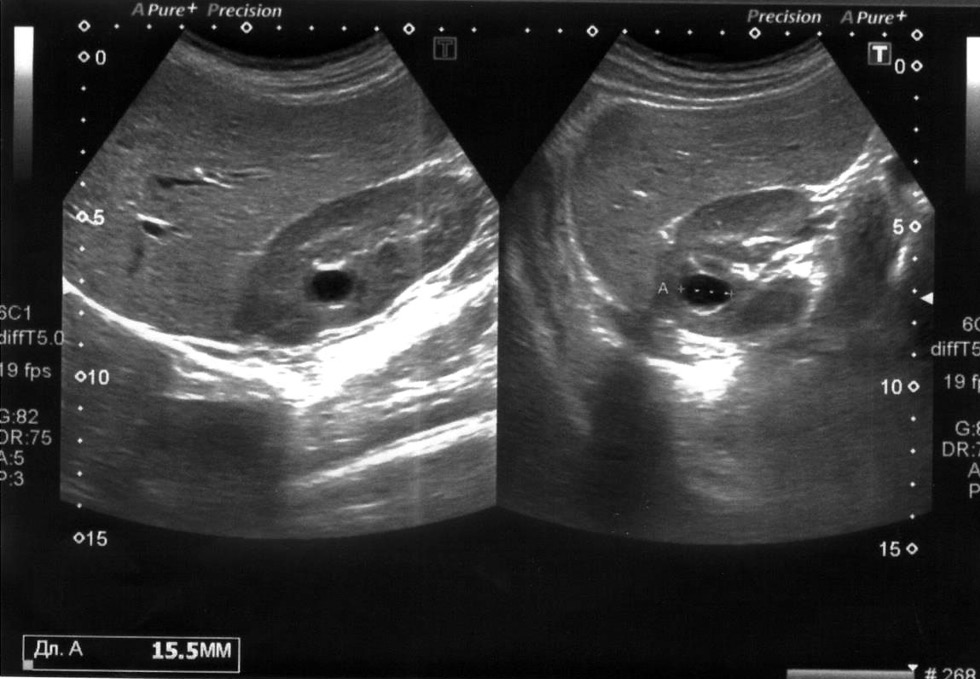

При ультразвуковом исследовании почек в среднем полюсе левой почки визуализируется анэхогенное аваскулярное образование с чёткими ровными контурами размером 15×14 мм. Заключение: Ультразвуковые признаки простой кисты левой почки (рис. 5).

Рис. 5. Ультразвуковое исследование почек: в среднем полюсе левой почки визуализируется анэхогенное образование с чёткими ровными контурами.